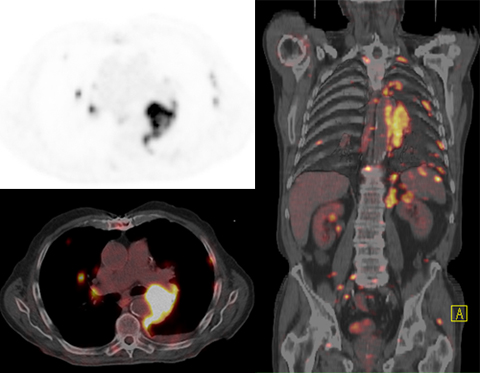

PET-CT(シーメンス)

PET画像

CTやMRIなどの診断機器は形態の変化でがんを発見しますが、PETは糖の代謝に基づいた画像で主にがんの発見に役立つ検査機器です。CTを組み合わせた一体型のものをPET/CTと呼び、診断能は向上します。 - 一度の検査で全身のスクリーニングが可能です

CT・MRなどの検査ではがんの可能性が高い部位を含む限定的な範囲の撮影が主流ですが(特にMRI)、PET/CTでは一度に全身の検査を行います。転移の有無なども調べることができ、また予想外の部位でがんが発見されたりすることもあります。 - PET/CT検査による被曝について